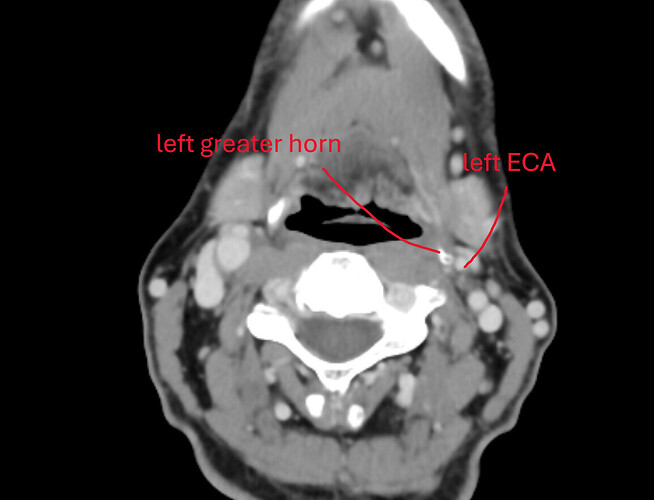

Sagittal view. Calcified portion of stylohyoid ligament. There is a little bit more in another slice, but this is the most of it.

3D views – one is low-res from above CT, and another is high-res from a CT with 0.2mm slices (most detailed CT I’ve ever seen). Distance from C1 is measured at about 1.5mm, length of calcified portion is ~15mm and it is flatter on one side in the lower section, with a “bit” sticking out slightly.

An animated gif with hyoid bone. Note the horns, left is quite lower than right.